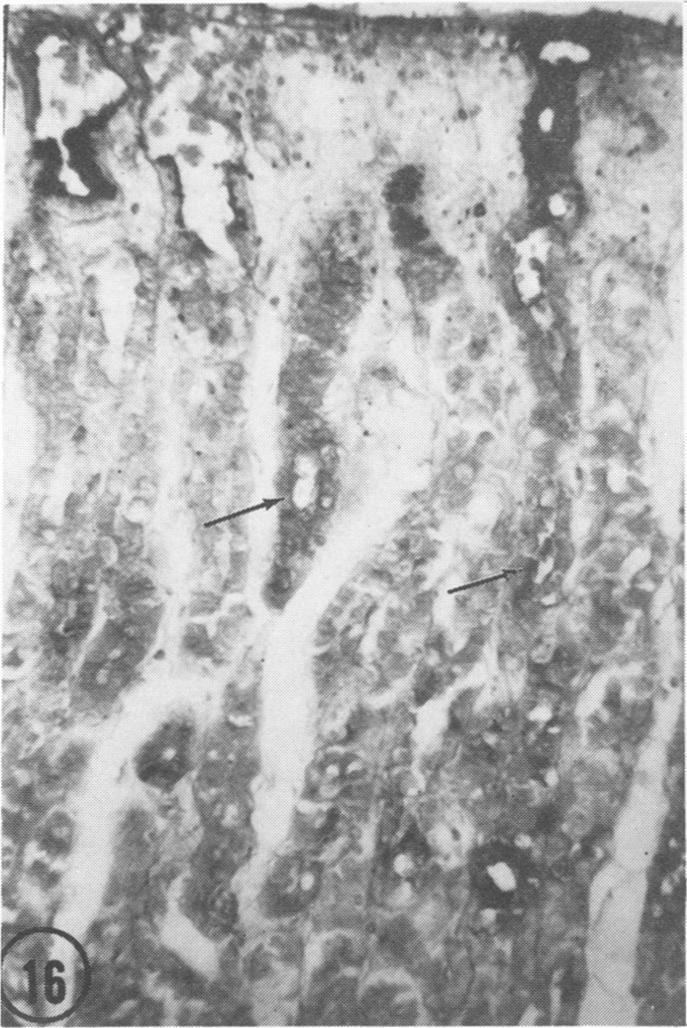

The several types of epithelial cells in human gastric mucosa produce different mucosubstances. The surface epithelium largely forms a neutral mucosubstance except that in about two-thirds of the specimens the deep foveolar cells produce a slight to moderate amount of a mucosubstance apparently containing sulfate esters and carboxyl groups. Mucous neck cells often exhibit a neutral mucosubstance but in about onehalf of the stomachs reveal a slight to moderate reactivity indicative of sulfated mucosubstance. Chief cells contain a sulfated mucosubstance with unique histochemical properties. Mast cells vary widely in prevalence but those in the gastric mucosa appear depleted of stored mucosubstances when compared with those in the gastric submucosa or the esophagus. The sulfated mucosubstance normally abundant in human as in canine chief cells appears consistently depleted in patients with stress ulcer or hemorrhagic gastritis. In addition, mucus often appears depleted in the surface epithelium and interstitial edema is present in the superficial mucosa of these patients. These findings appear consistent with the view that biosynthetic activity in chief cells and surface epithelial cells is impaired perhaps secondary to shock-induced circulatory changes in gastric mucosa of patients with stress ulcer or hemorrhagic gastritis.